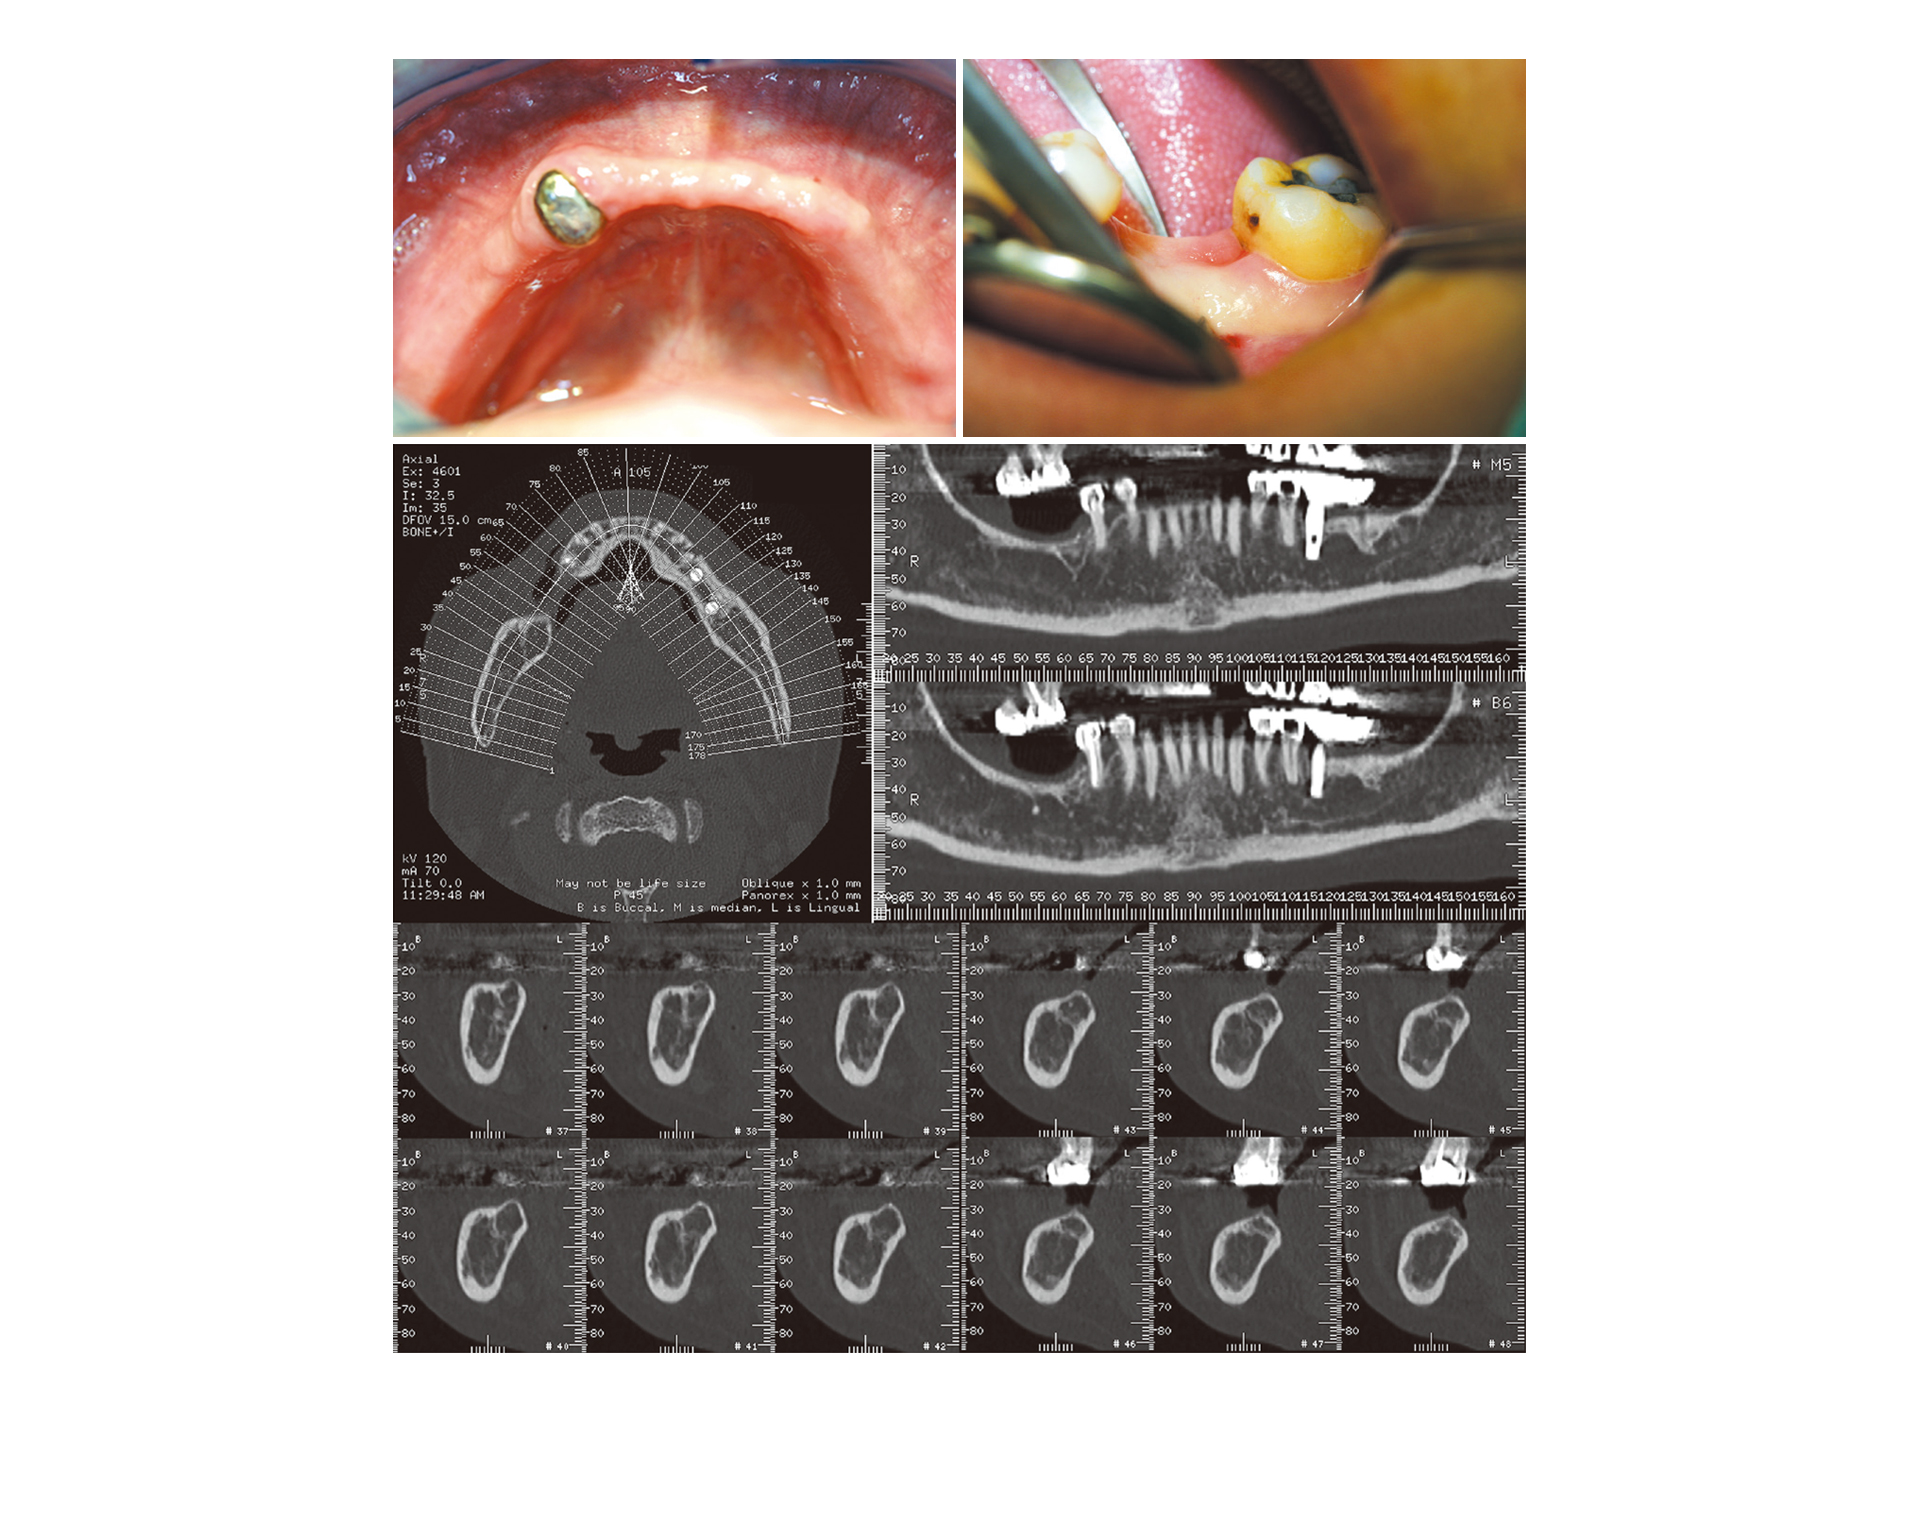

급속 골이식(i-GBR)은 치아를 발치하는 순간 즉시 골이식재와 천연 콜라겐 차폐막을

함께 이식하여 골재생과 잇몸재생에 매우 탁월한 결과를 보입니다.

급속 골이식은 치유능력이 가장 좋은 시기인 ‘발치 직후’를 잘 활용하여

수직 수평적으로 많은 양의 뼈와 두꺼운 각화치은을 얻을 수 있으므로

하지만 연세굿데이에서 독자적으로 개발한 ‘급속 골이식(i-GBR)’은

발치와 동시에 뼈이식+콜라겐 차폐막+PDRN(연어주사)를 적용함으로써

치조골이 주저앉는 것을 막아주어 튼튼한 임플란트 식립이 쉽게 가능합니다.

치과계 최초 Hidden X 봉합술 적용

잇몸을 끌어당기지 않아 출혈 거의 없음

콜라겐 차폐막을 이용한 Open healing 마무리